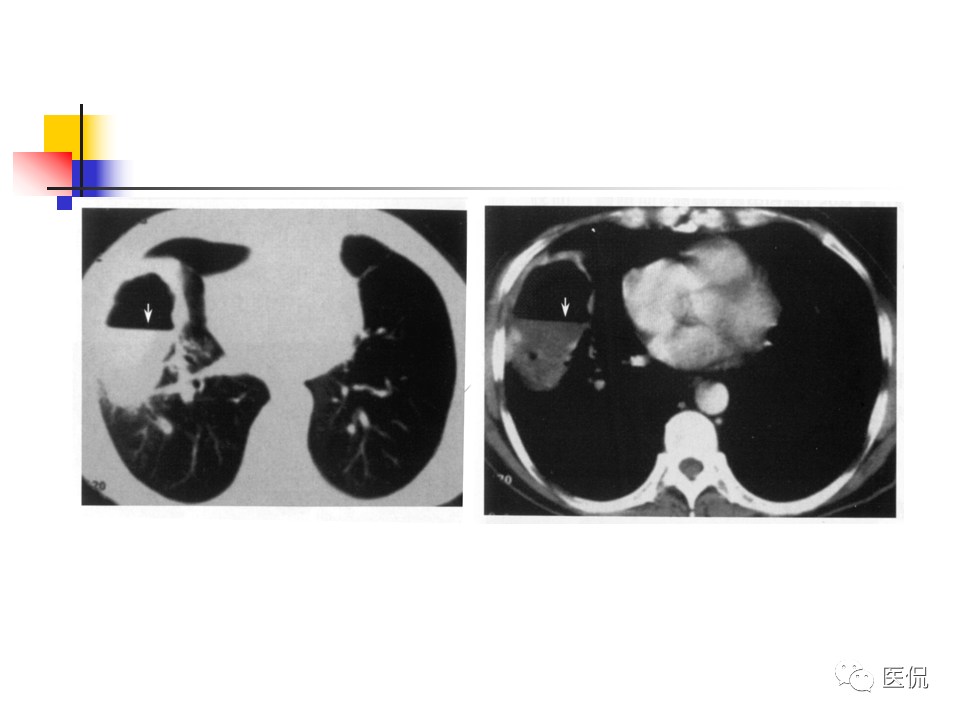

大叶性肺炎|大叶性肺炎的影像诊断

大叶性肺炎影像诊断